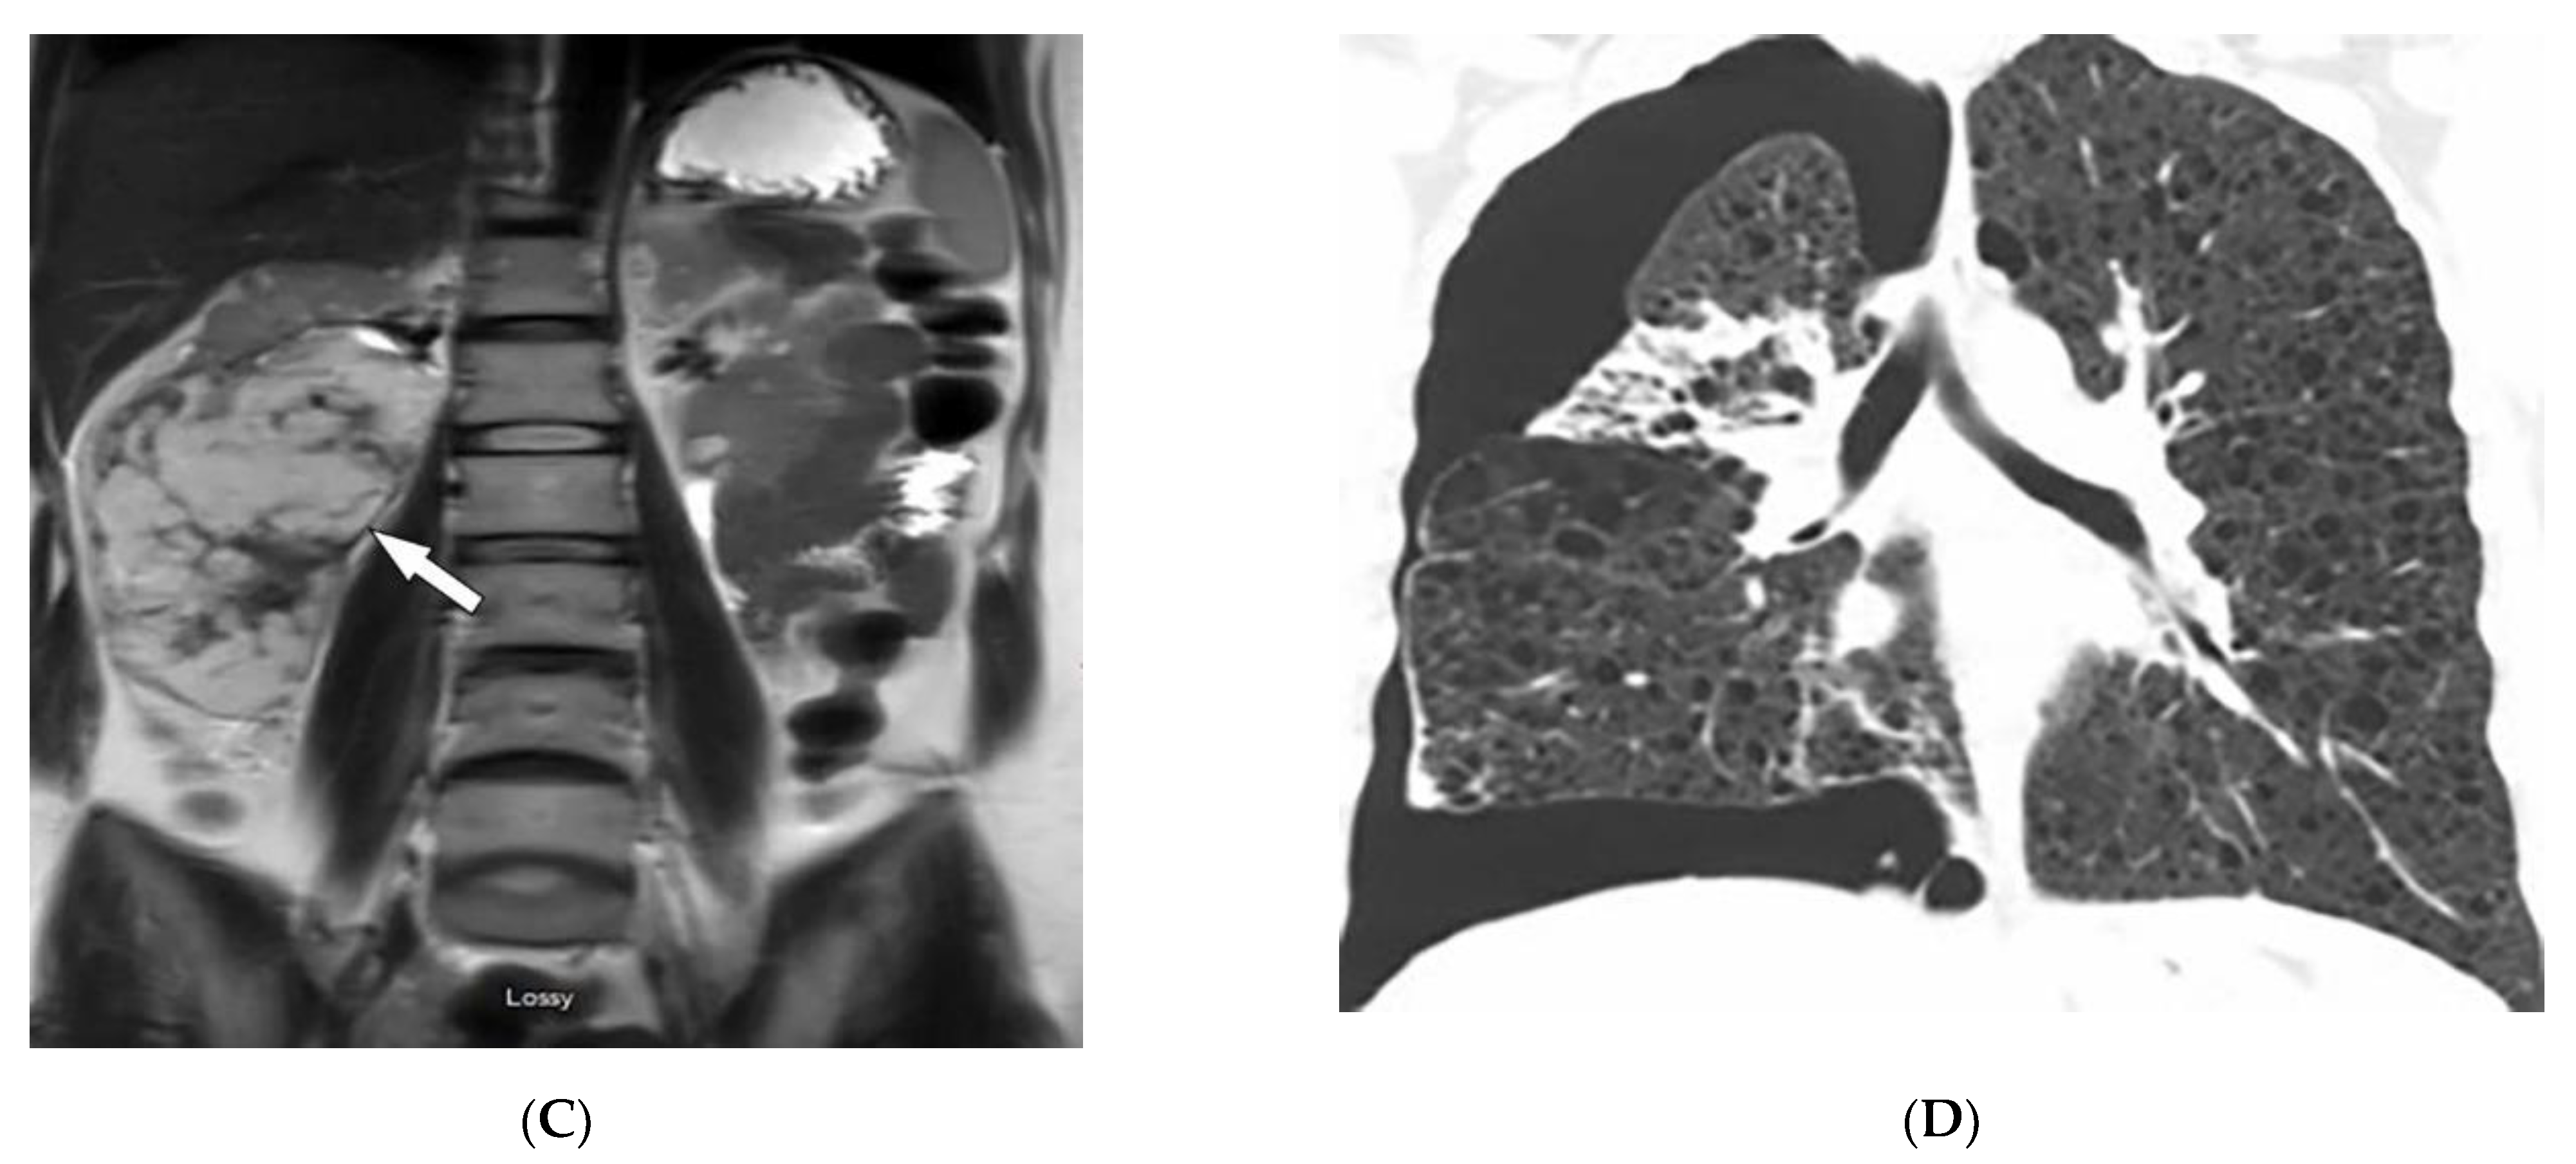

| Birt–Hogg–Dube syndrome | Fibrofolliculomas, trichodiscomas, acrochordons Lung cysts (pneumothorax) Renal cysts | Bilateral basilar predominant, thin-walled cysts abutting pleura and pulmonary vessels |

| McCune–Albright syndrome | Cafe’-au-lait macules Fibrous dysplasia Endocrine dysfunction | Medullary ground-glass lytic lesions with thin cortices Various sclerotic to cystic pattern |